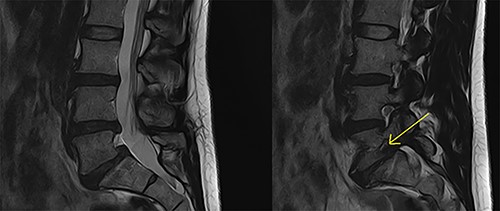

This 45-year-old female presented with low back pain and right-sided L5 radiculopathy involving pain and sensory symptoms extending into the leg. Her symptoms began following an acute event involving a bend, twist and lift injury. She trialled conservative measures, including analgesia, physiotherapy and perineural injections, over a period of 6 months, with persistent symptoms. Imaging revealed bilateral L5 pars defects and a Grade 1 spondylolisthesis resulting in foraminal stenosis with bilateral compression of the exiting right L5 nerve roots. In addition, degenerative disc disease was present at both L4/5 and L5/S1 with contact of the right L5 nerve root in both the right L4/5 lateral recess as well as within the right L5/S1 foramen (Fig. 1). A single photon emission CT bone scan was additionally performed, demonstrating significant uptake in the L4/5 and L5/S1 facet joints. Based on these findings, L4/5 and L5/S1 PLIF were recommended. The patient proceeded to surgery with CFR-PEEK pedicle screws (CarboFix, TelAviv, Israel) and PEEK interbody cages (Evolution Spine, Sydney, Australia) inserted at both levels. Operative time was 3.5 hours, with 240 ml of blood loss and no intraoperative complications.

Preoperative MRI lumbar spine (mid- and para-sagittal slices of T2 weighted sequence) demonstrating posterior bulging of the L4/5 and L5/S1 discs in conjunction with a Grade 1 spondylolisthesis of L5 on S1 resulting in significant right-sided foraminal stenosis at L5/S1 (indicated by yellow arrow).